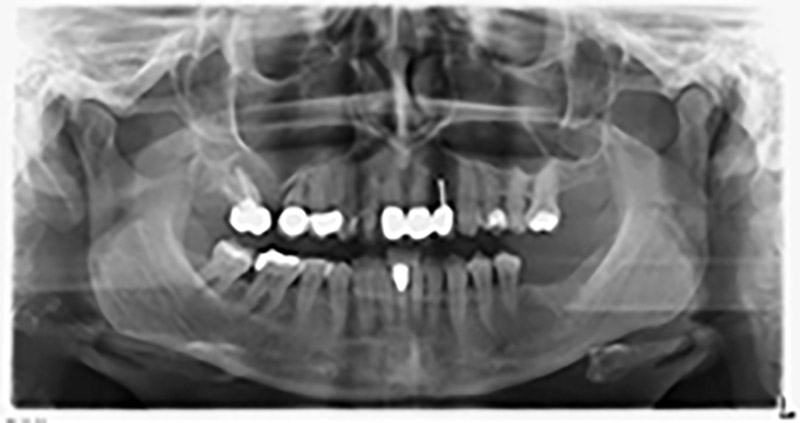

The 59-year-old patient presented with an advanced case of periodontitis, describing an unpleasant feeling and poor taste from the first quadrant in a distal direction. The clinical examination revealed generally enlarged periodontal pockets and very advanced bone atrophy in regions 16 and 14. The radiology confirmed the findings (Fig. 1). Teeth 16 and 14 could not be retained.

Image 1: Orthopantomogram with bone atrophy in region 16–14. *

About six months after teeth 16 and 14 were extracted, a digital volume tomography (DVT, Planmeca) examination was performed for planning and risk minimization purposes. It clearly showed that the bone had not regenerated to the desired volume (Fig. 2 to 7).

A sinus floor elevation is required in both region 16 and region 14 to guarantee a fixed restoration based on at least two implants. Relatively large-scale bone augmentation is required due to the residual bone volume being extremely low in this case. Major bone augmentation procedures are invasive and linked to higher patient morbidity, as well as being time-consuming and expensive. It is more difficult to predict the results of the treatment and the risk of failure is increased. The patient was informed of the increased risk and was offered a removable solution, which she consistently rejected.